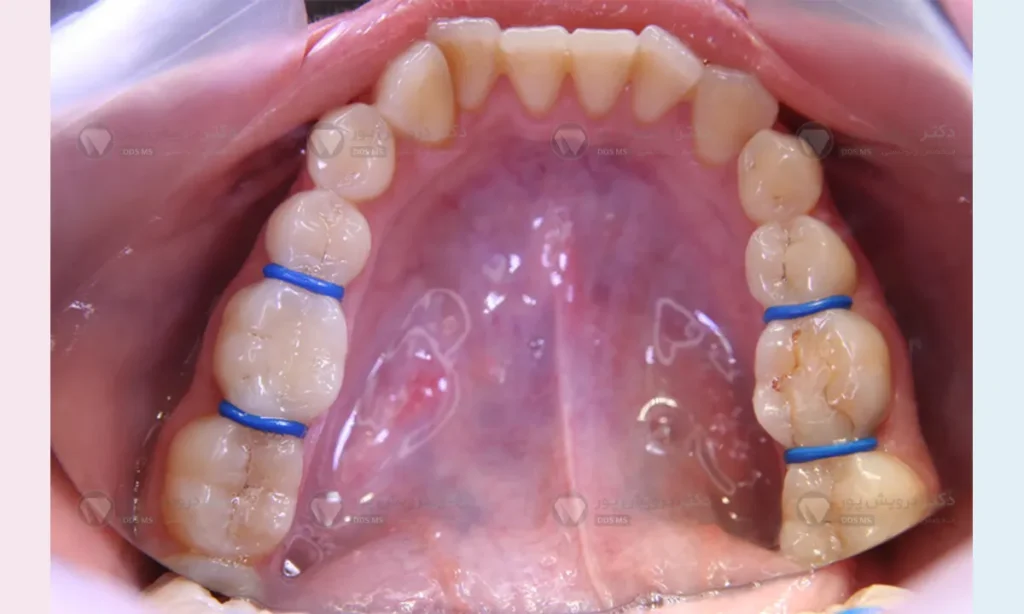

متخصص باید بین دندان های آسیاب شما کمی فاصله ایجاد کند تا حلقه فلزی بتواند از بین آن ها رد شود. برای این کار از کش های بسیار کوچکی به نام سپراتور یا جداکننده استفاده می کند. این کش ها چند روز بین دندان های شما می مانند و فضا را به آرامی باز می کنند. شاید در روزهای استفاده از این کش ها، کمی احساس فشار یا دندان درد خفیف داشتهباشید که کاملا طبیعی است و نشانه حرکت دندان است.

در جلسه دوم …

وقتی به مطب مراجعه می کنید کش ها برداشته می شوند. حالا یک فاصله میلی متری و عالی بین دندان ها ایجاد شدهاست. دکتر سایزهای مختلف بند ارتودنسی را امتحان می کند تا دقیقاً سایزی که فیت و قالب دندان شماست را پیدا کند. بعد از پیدا کردن سایز مناسب، داخل حلقه را با یک سمان یا چسب مخصوص که معمولاً حاوی فلوراید است پر می کند و آن را روی دندان فشار می دهد تا کاملاً سفت و ثابت شود.